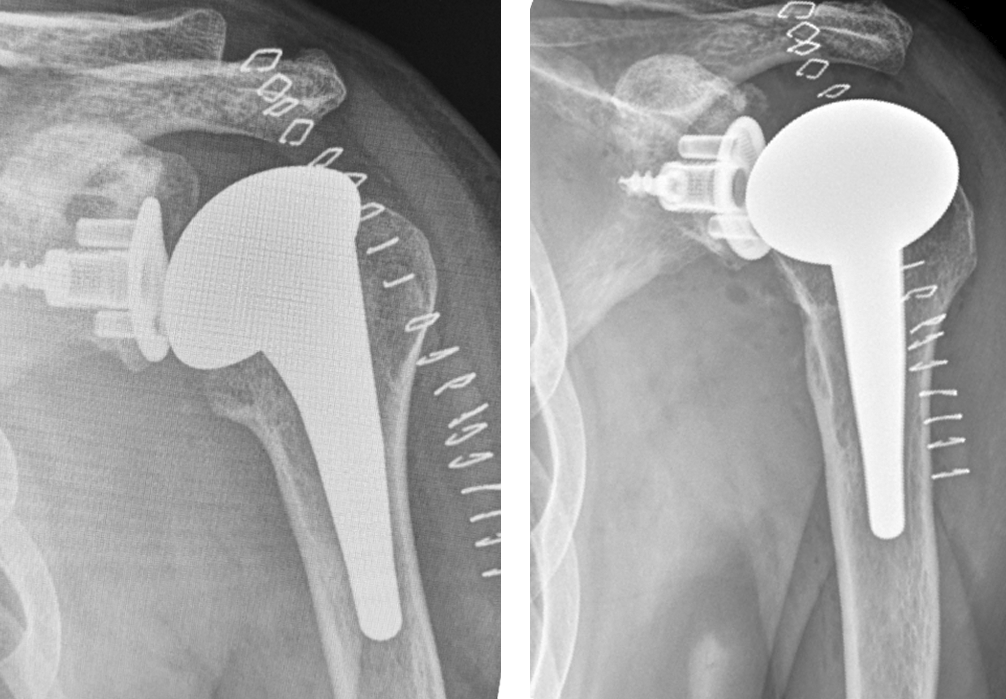

Post-op

Implantation of the LINK Embrace

- Short Stem, uncemented

- Head Adapter 4 mm offset

- Humeral Head 47 mm diameter, height M

- Convertible Glenoid with Metal-Back, with the TrabecuLink structure for bone integration with central screw and UHMWPE-Insert

Result:

- Good stability

- Good ROM

- Good offset restoration